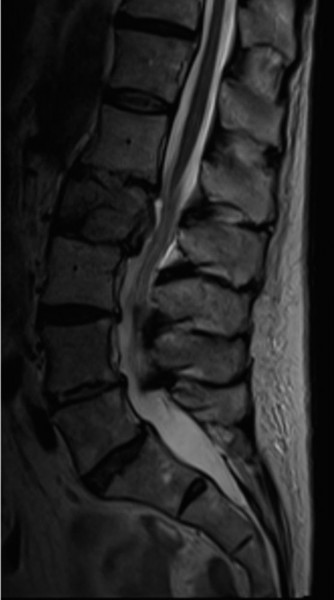

Prognosis of central cord syndrome? Indications for surgery for this disorder? CASE 2 A 56-year-old man presents to you with a chief complaint of severe right buttock, posterior thigh, and lower leg pain for 12 weeks. It radiates to the lateral aspect of his foot, and it is worse with sitting or standing for prolonged periods and with walking. Now over the past 2 weeks, he reports difficulty with toe push-off on the right side. Treatment so far has been nonsteroidal anti-inflammatory drugs (NSAID), physical therapy, and an epidural injection without significant relief. Physical examination findings include 4/5 right ankle plantar flexion, a positive straight leg raise on the right, and an absent right Achilles tendon reflex. Images of his lumbar spine are shown in Figures 1–4 and 1–5.

Figure 1–5

The correct answer is (C). The patient presents with classic right S1 radiculopathy and new onset plantar flexion weakness. The images demonstrate a right-sided paracentral disc herniation at L5/S1 compressing the traversing S1 nerve root. Despite nonoperative management, he continues to have severe pain and new weakness. Continued physical therapy or an epidural injection is unlikely to improve the patient’s pain at this time. In the setting of neurological decline, surgery is more strongly indicated. Lumbar discectomy is the most appropriate procedure for this patient. Fusion would only be indicated if there were radiographic signs of instability, which are not present.